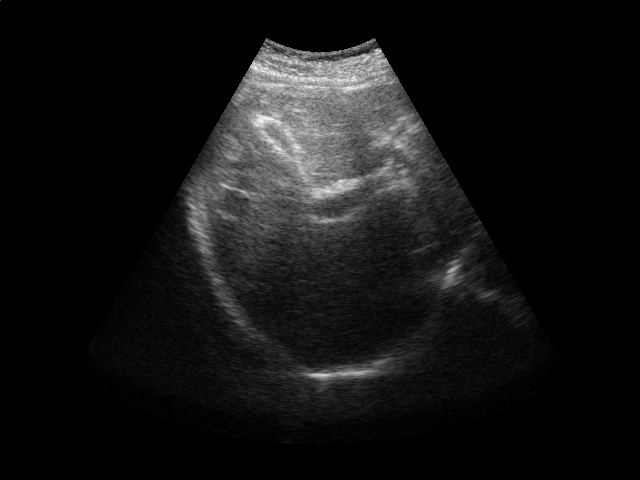

Refer to caption

Figure 2: Ultrasound gating. Top: Ultrasound images of the liver over time (abdomen, right upper quadrant). Bottom left: Correlation coefficient vs. error tolerance ε𝜀\varepsilon. Bottom right: The number of support vectors vs. error tolerance ε𝜀\varepsilon. Both figures in the bottom report results for different values of kernel ridge regression regularization parameter λ𝜆\lambda.

Respiratory gating tracks a patient’s breathing cycle, which has numerous applications such as 4D imaging, radiation therapy, and image mosaicing [16]. Manifold learning has been used for highly accurate respiratory gating of ultrasound images [23], where 4D data reconstruction was achieved with retrospective gating, i.e., the gating was calculated after the data acquisition was finished. We extend this work to attain real-time gating. A small number of breathing cycles are acquired and used as input for manifold learning to construct the respiratory signal, as is done for retrospective gating. The new incoming stream of ultrasound images is then gated by performing an out-of-sample extension.

We conduct experiments on five 2D ultrasound image sequences of the human liver acquired during free breathing; example images are shown in Fig. 2. Each sequence contains 640×\times480-pixel images and vary in length between 298 and 371 frames captured at 33 Hz. For a given image sequence, we use each image in the sequence as an input data point for learning a 1D manifold with Laplacian eigenmaps [4]; we use a 9-nearest-neighbor graph with an associated heat kernel of temperature t=10𝑡10t=10. The 1D embedding learned using an entire sequence of images serves as a reference signal for evaluating our sparse out-of-sample extension versus kernel ridge regression as the baseline. In what follows, we compare the 1D embedding of our sparse out-of-sample extension to the reference signal by computing a correlation coefficient between them. We use kernel ridge regression as a baseline method. Here we train on the first 200 frames and test on the remaining frames. We then compare the results with those obtained by training on all frames, as would be done for retrospective gating.